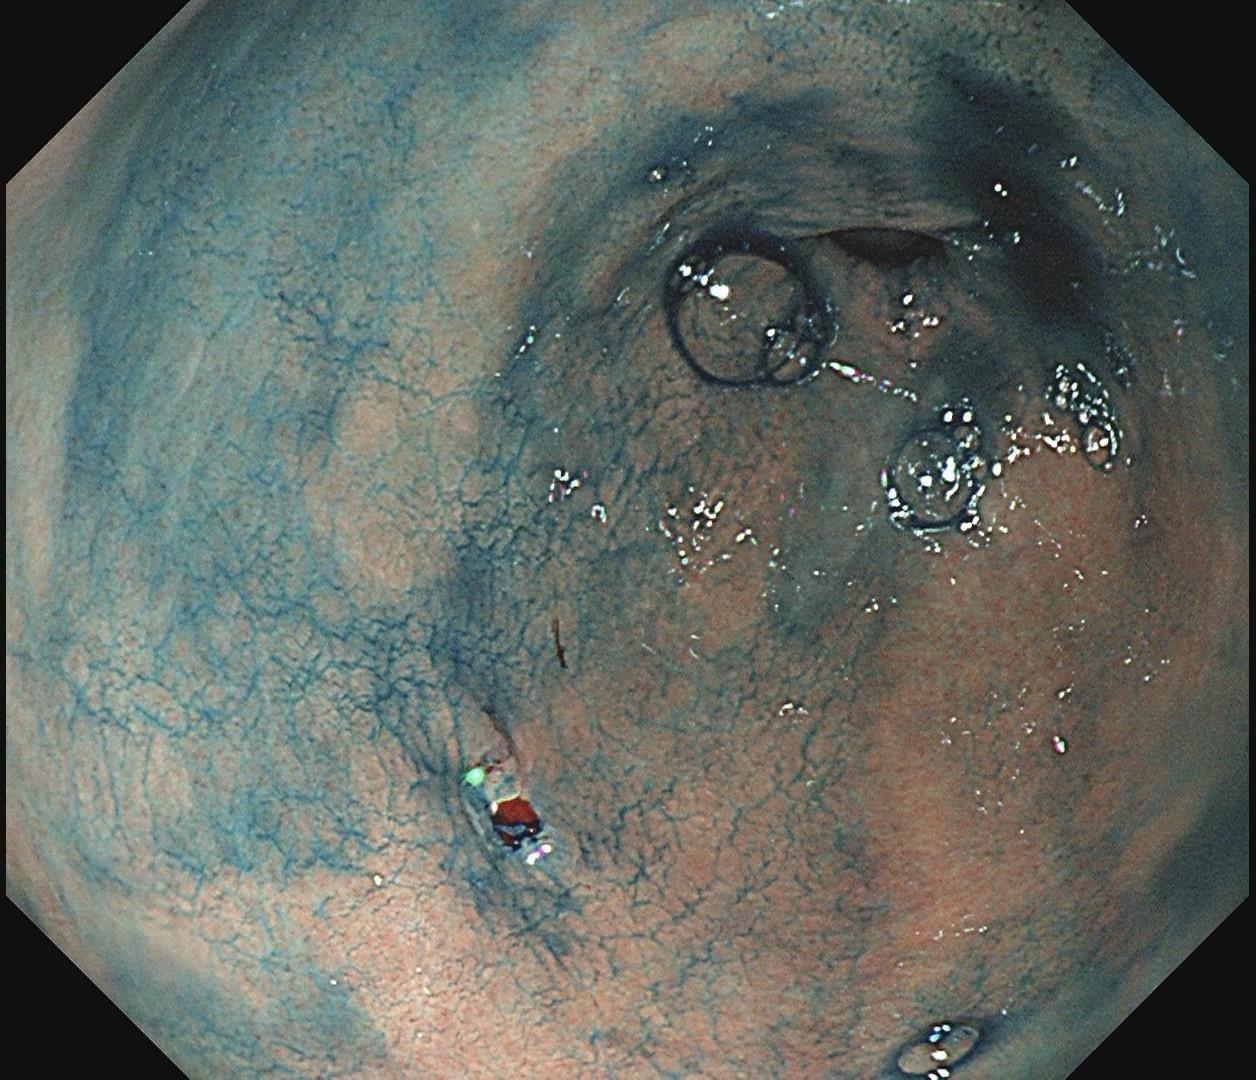

小小的糜烂一枚。这样的病灶,就算结果是阴性的,也很有意义~